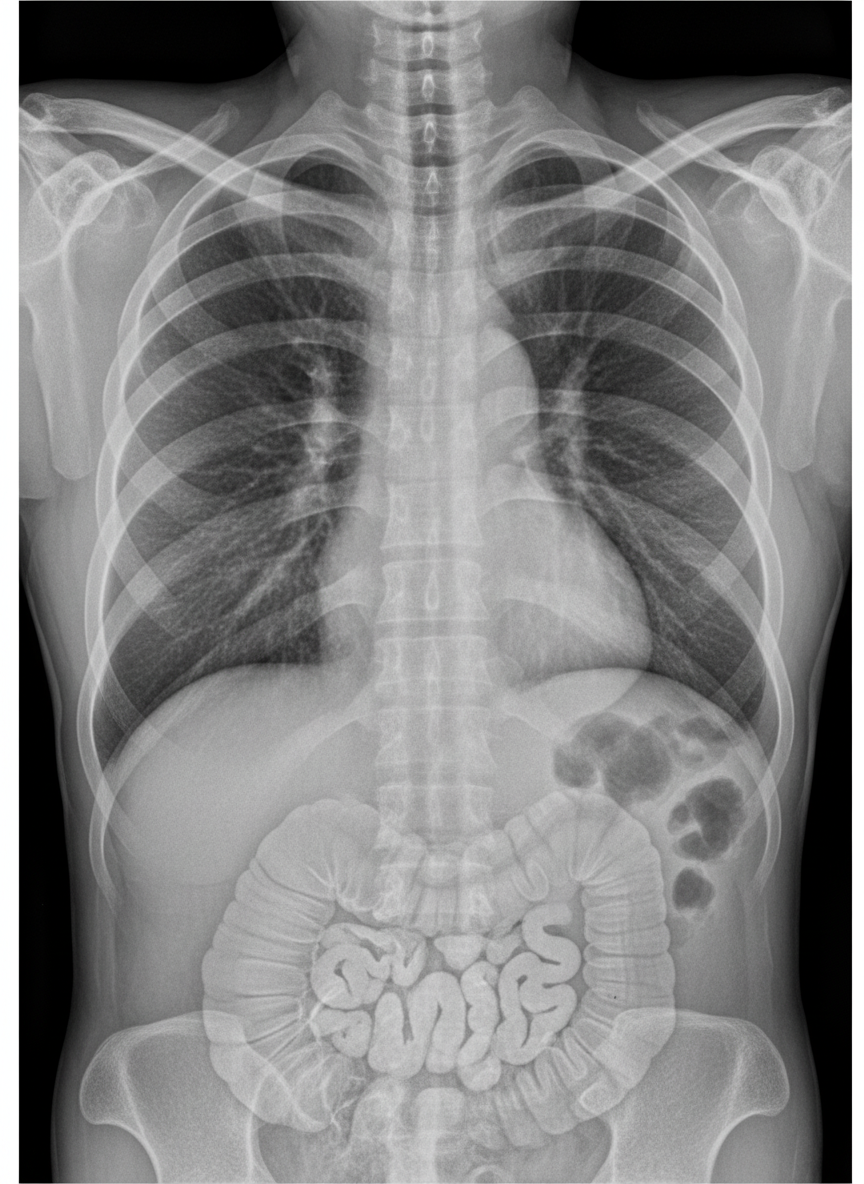

An X-ray shows findings suggestive of:

Explanation: ***Pseudopneumoperitoneum*** - Shows **bowel haustrations** beneath the right hemidiaphragm, indicating **Chilaiditi sign** (bowel interposition between liver and diaphragm). - This is a **benign condition** where the colon mimics free air but contains characteristic **colonic markings**. *Pseudopneumomediastinum* - Would show **mediastinal air-like appearance** caused by **bowel gas** in the mediastinum, not subdiaphragmatic location. - Typically involves **esophageal** or **gastric** structures creating false mediastinal air impression. *Pneumoperitoneum* - Shows **true free air** in the peritoneal cavity without **bowel wall markings** or haustrations. - Usually indicates **bowel perforation** requiring urgent surgical intervention, unlike the benign Chilaiditi sign. *Pneumomediastinum* - Presents as **actual air** in the mediastinal space, often outlining cardiac borders and great vessels. - Commonly caused by **alveolar rupture**, **esophageal perforation**, or **chest trauma** with air tracking into mediastinum.